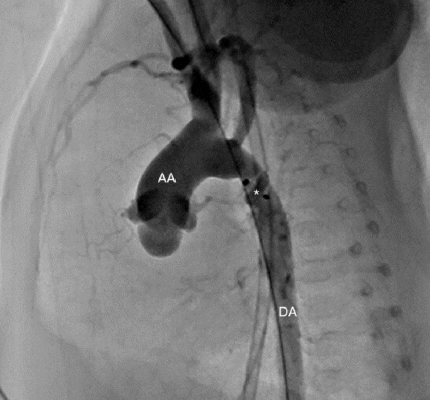

Late Aortic Obstruction Post Patent Ductus Arteriosus Closure Managed with Renata Minima Stent

Read Full Study